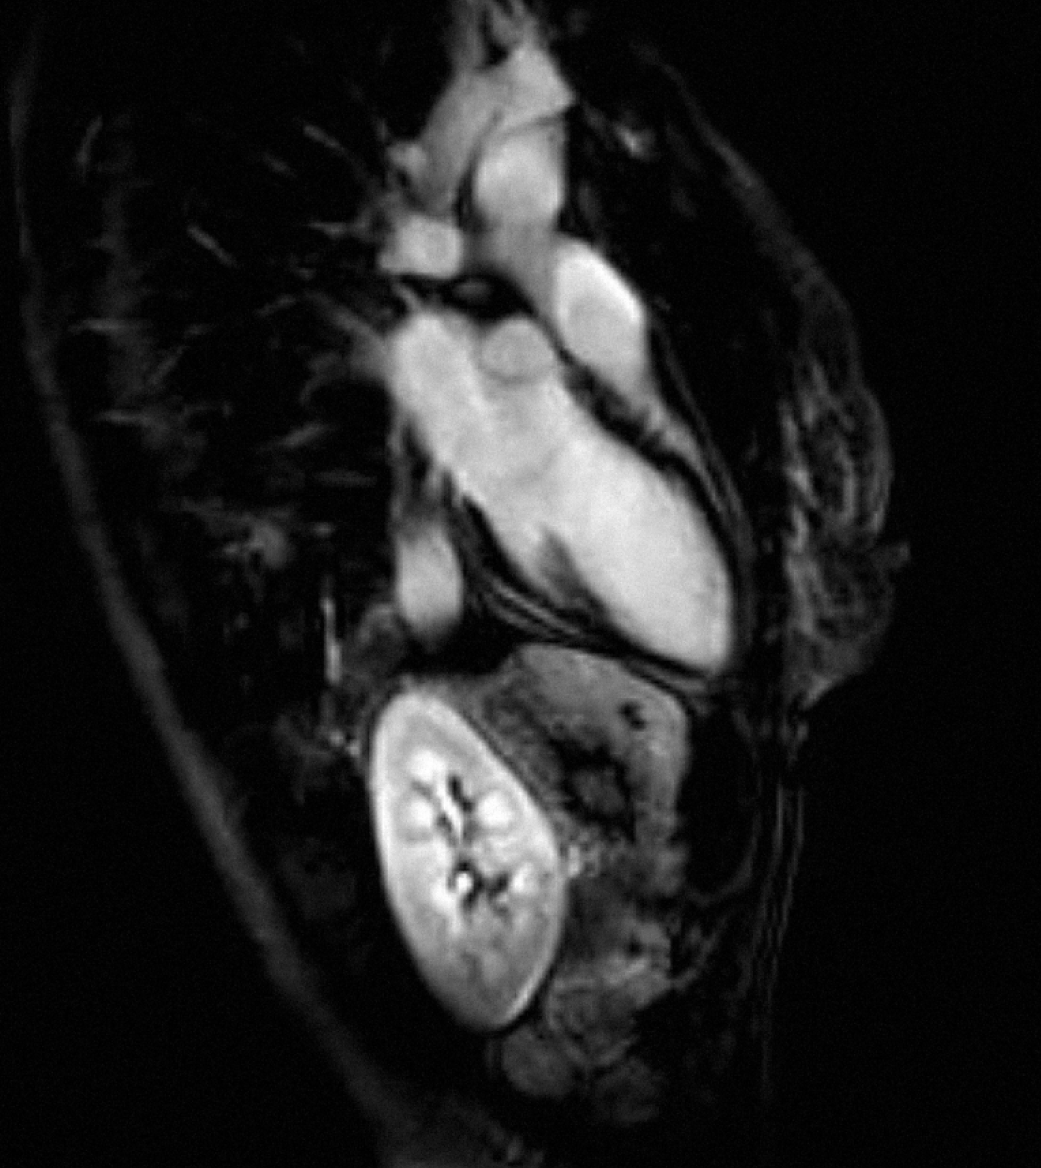

A 51-year-old Caucasian female with a past medical history of depression underwent dental procedure. She had no allergy, no history of smoking or alcohol consumption, and no family history of heart disease. The dentist injected a solution of 2% xylocaine into gum. Three minutes following the procedure, the patient complained for chest pain, during one hour. She was admitted to a cardiac intensive care unit. Her blood pressure was 125/65 mmHg, her pulse rate was 70 beats per minute (regular), and her spontaneous arterial oxygen saturation was 97%. Her physical examination was normal. Her electrocardiogram (ECG) revealed T waves inversions in AVF, DII, DIII, V4, V5 and V6 (Figure 1). Troponin level performed at admission was 23 ng/mL (N=0,05). C-reactive protein (CRP) concentration was normal. Chest X-ray was normal. Cardiac catheterization and ventriculography were normal. An early trans-thoracic echocardiogram and cardiac MRI found a global left ventricular hypokinesis with depressed ejection fraction of 40%, without late gadolinium enhancement (Figure 2)

(Figure 3) (Figure 4). Chest pain stopped the first day and the patient was discharged from hospital six days later, with beta blocker treatment (bisoprolol 5 mg/day). Left ventricular ejection fraction has been checked normal (65%) after five weeks of treatment. We concluded to atypical TTC induced by injection of xylocaine.